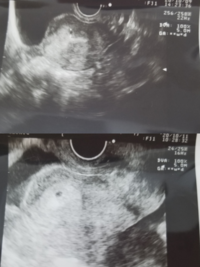

胎嚢の平均的な大きさ 4週目:まだ見えない 5週目:1673mm 6週目:2394mm 7週目:3011mm 8週目:43mm 9週目:5196mm 上記は三重大学医学部の資料による数値です。 胎嚢は妊娠週数が進むにつれて大きくなっていきますが、上記数値はおおよその胎嚢の大き 胎嚢は早ければ妊娠4週のはじめに確認でき、一般的には 妊娠4週末から妊娠5週頃 までに見えます。 ただ妊娠週数は数え間違うこともあるため、妊娠5週頃に胎嚢が見えない場合はもう1週ほど期間をおいて超音波検査を再度行います。

妊娠週数と心拍についてです。 今日で7週4日なのですが、仕事がバタつき今日初めて受診しました。 ですが、週数は5週で小さいねと言われて胎嚢が10ミリしなかったです。これは流産してる可能性が高いのでしょうか? ちな 5週目は「見えればok」だそうで、大きさは気にしないで大丈夫とのこと。 本日8ミリでした。 エコー写真も貰いました! 次は一週間後です。 無事、胎嚢が大きくなって、6週目を越えられますように!!!!2 妊娠5週で胎嚢が確認された場合、1~2週間後に再診し a 胎嚢が大きくなっているか ( 1日1ミリ大きくなります ) b 胎嚢内に卵黄嚢 ( yolk sac 白いリング ) があるか c 胎児心拍 を確認します。卵黄嚢の確認をもって胎嚢と確定されます。

5w4dと思われる日にエコー撮りました。 171mmとのことで胎芽になっていくであろう物も確認できました。 二週間後の診察が楽しみであり不安ですが、リラックスして待とうと思います。 おなまえ moco ねんれい 38 妊娠週 5w4d 4回目のAIH、5w4dで胎嚢&卵黄嚢 胎嚢は、早ければ「妊娠4週後半」から確認できるようになります。 なお、妊娠4週は、妊娠していない場合の生理予定日の週です。 超音波検査の画像で見ると、胎嚢は「黒い円」のような形で、「周囲に白い縁取り(=絨毛膜)」があります。 妊娠5週前半になると、胎嚢の中にリング状